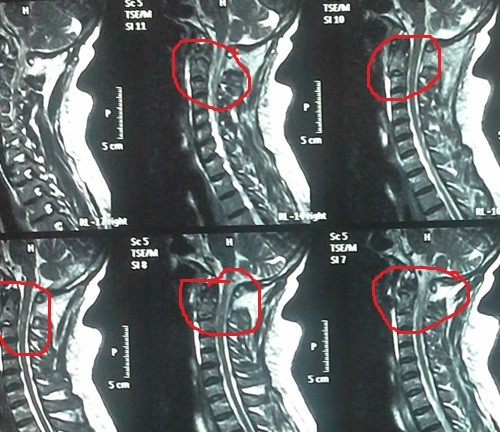

fracture of the second cervical vertebra with displacement between the second and third cervical